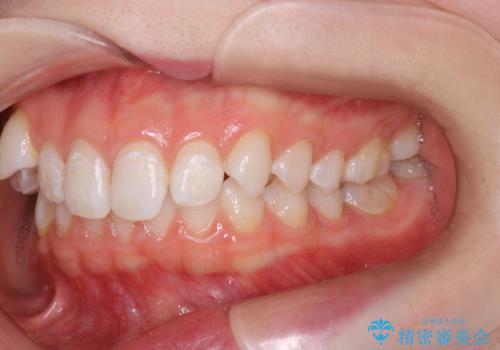

- 右上の八重歯と歯のデコボコ、そして上下の歯の中心(正中)のズレを気にされて来院されました。精密な検査の結果、歯が並ぶスペースが不足しているため、上顎の小臼歯(前から数えて4番目の歯)を抜歯し、そのスペースを利用して歯並び全体を整える治療計画を立案しました。これにより、八重歯の位置を適切に改善し、叢生(歯のデコボコ)を解消するとともに、上下の正中線のズレも改善することを目指します。

今回の矯正治療では、歯が並ぶスペースを確保するため、上顎の小臼歯を抜歯しました。抜歯によってできたスペースを有効活用し、ワイヤーやブラケットを使って右上の八重歯を適切な位置へ移動させ、叢生を解消していきました。また、治療を通じて上下の歯の中心である正中線のズレも改善するよう、慎重に歯を動かしました。治療の結果、長年気にされていた八重歯と歯のデコボコが解消され、上下の正中線も一致。機能的にも審美的にもバランスの取れた、美しい歯並びと笑顔を獲得していただけました。